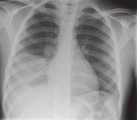

Специфических методов диагностики аспирационной пневмонии нет. Диагноз устанавливается по совокупности ряда синдромов и симптомов: гипоксемии, лихорадки, лейкоцитоза, легочной инфильтрации типичной локализации и доказанной или предполагаемой аспирации у пациентов с факторами риска. Кроме общего осмотра, проводится рентгенография легких, бронхоскопия, исследование мокроты, КТ, исследование крови.